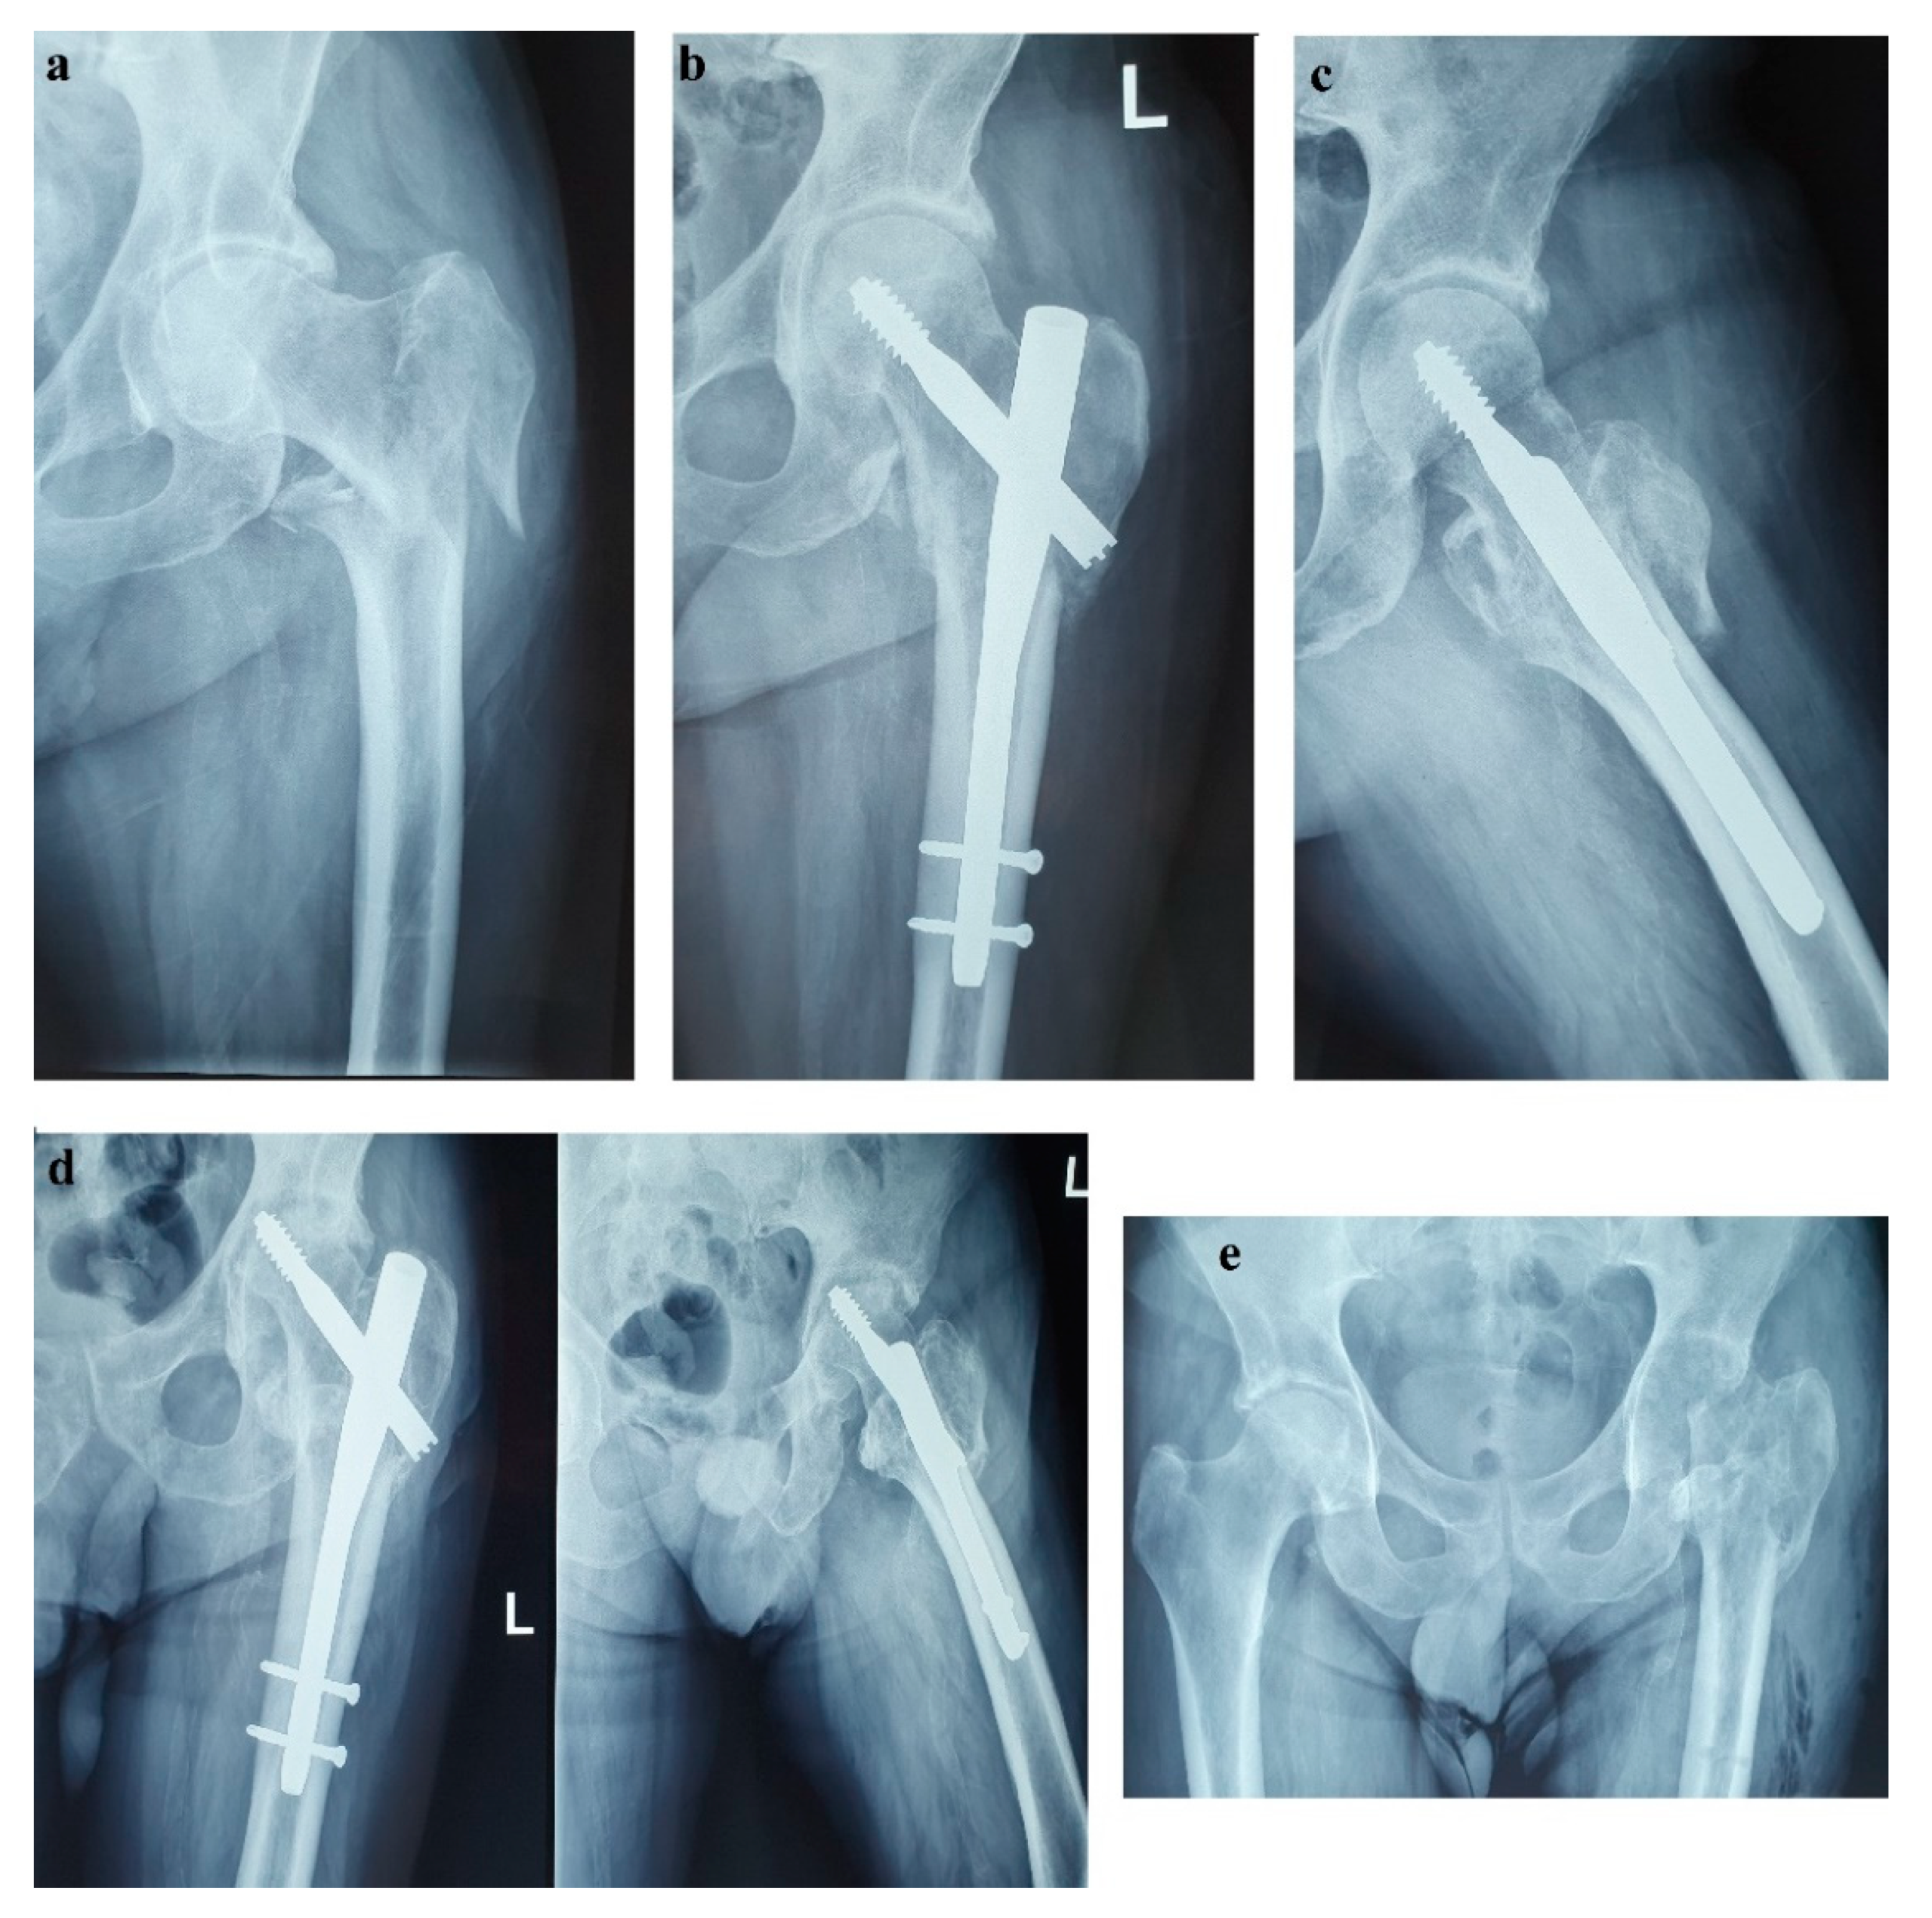

Unfortunately, in October 2017, the patient fell from standing height and suffered a left pertrochanteric comminuted fragility fracture, and osteosynthesis with gamma nail was performed (Figure 2a–c). The immediate evolution was further complicated by wound dehiscence that called for surgical debridement.

In the spring of 2019, the patient maintained clinical remission of the hormonal syndrome and stable disease imaging. Nonetheless, he presented with a purulent cutaneous fistula at the incision level performed for the pertrochanteric fracture. Following orthopedic and biological evaluations, hip radiography and bacteriological examination, necrosis of the femoral head with a “cut-out” phenomenon was diagnosed as a possible complication of the previous glucocorticoid therapy (Figure 2d). Vancomycin and clindamycin-sensitive Staphylococcus epidermidis and Klebsiella were identified in the fistula secretion and treated with antibiotics. Due to this septic situation, the ablation of the implant and the surgical sanitation of the hip septic foci were mandatory. Meanwhile, the patient maintained spontaneous INR values of 3–5, which was difficult to manage in the perioperative septic setting. Lastly, the ablation of the osteosynthesis material and the Girdlestone-type femoral head resection arthroplasty were performed (Figure 2e). No intra- or periarticular purulent collections were detected intraoperatively. False membranes from inside the implant were collected and the same staphylococcus epidermidis was identified.

Figure 2. (a) Left (L) pertrochanteric fragility fracture; (b,c) Gamma nail osteosynthesis; (d) Femoral head osteonecrosis and cut-out complication; (e) Girdlestone resection arthroplasty.